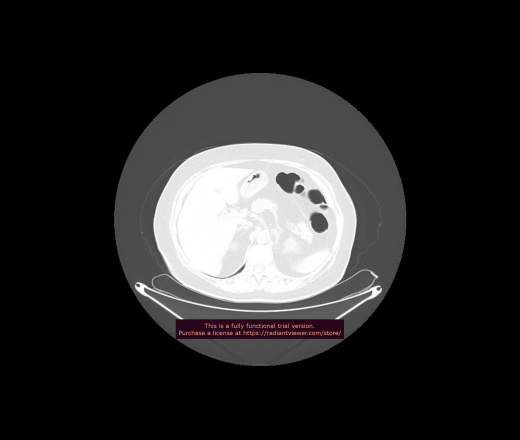

Уважаемые коллеги, если имеется интерес, сможете ли Вы спрогнозировать дальнейшее +-одинаковое течение процесса у 4 данных разных пациентов? Зацепиться где-то можно очень просто, где-то нельзя.